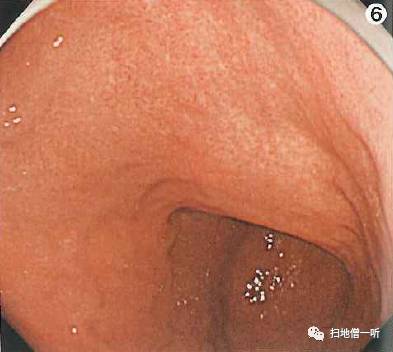

A:胃癌在图6。HP感染胃癌。

背景粘膜为C-2型萎缩。体部淡红色弥漫发红提示HP感染。体下部大弯侧可见小片褪色斑,周围未见相同表现病灶。

接近观察可见褪色斑边界较清晰

靛胭脂染色后可见HP感染的周围胃小区大小不等,与病灶处胃小区未见明显差别,表面凸凹不明显,怀疑印戒细胞癌

最终病理诊断:

胃体下部前壁,O-IIc,6mm,sig,T1a (M),UL(-)

小结:萎缩的褪色改变与未分化的褪色改变需加以辨认

补充说明:图4可见体部小弯多发褪色斑,呈纵行排列,判断为非萎缩境内的局灶萎缩表现。